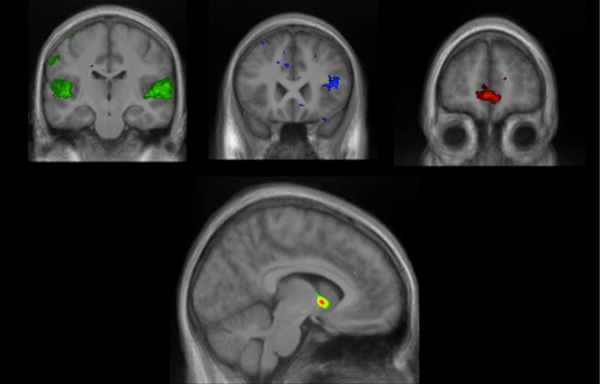

SOUNDS GOOD Listening to new music sparks activity in brain regions that analyze sound (green), recognize patterns (blue), process emotions (red), and determine rewards (rainbow, at bottom).